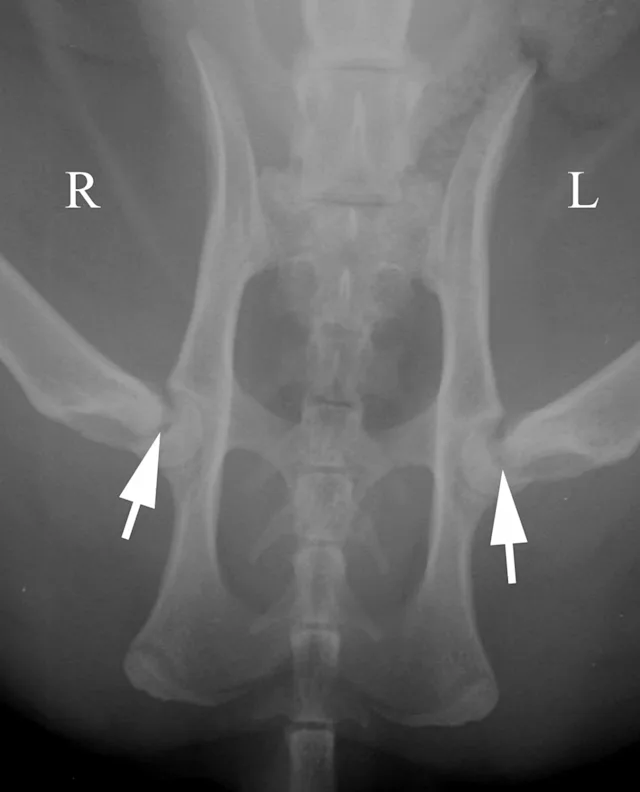

Pelvic radiographs must be assessed for adequate positioning and should be repeated if the pelvis is oblique, as in Figure 2A. In this example, there are multiple positioning errors. The right femur/stifle should be further internally rotated (so the patella is more centrally located over the femur). The right stifle should be moved axially (medially) so the femurs are parallel. The pelvis is rotated with the right hemipelvis farther away from the imaging plate. In Figure 2B, the right hemipelvis has been elevated from the imaging plate. In this image, the right (up) obturator foramen is increased in width compared with the left. Additionally, the left (down) ilium appears narrower.

Oblique positioning will result in false assessment of dorsal acetabular rim coverage of the femoral head, as shown in Figure 2C. The dorsal acetabular rim (white arrows) appears to provide more coverage of the right femoral head and less coverage on the left side. When the patient is properly positioned, as in Figure 2D, it is evident that coverage of the dorsal acetabular rim (white arrows) is similar on both sides.